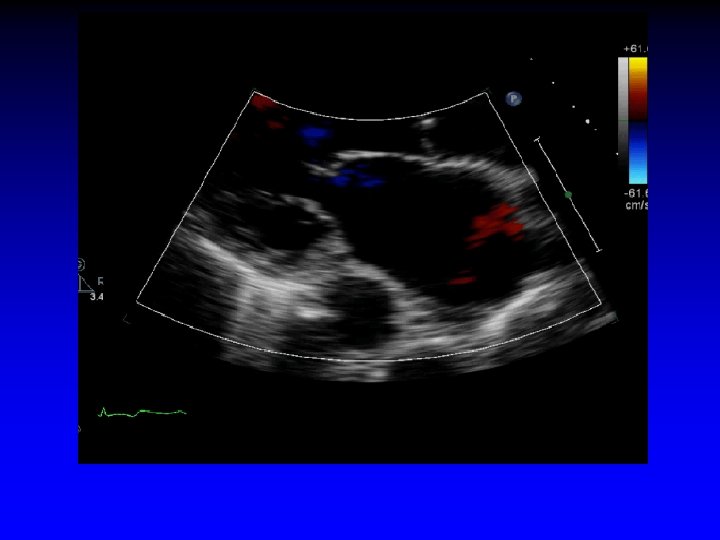

Case 7 Ischemic MR restricted PML

Increased tenting area